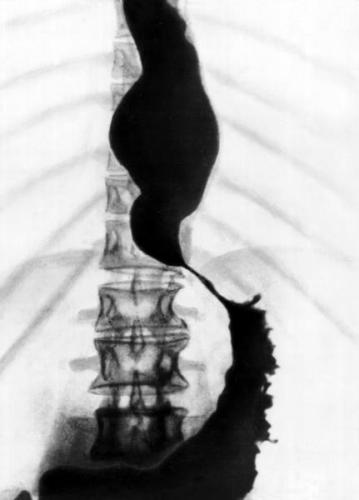

- рентгенологическое контрастное исследование – пациенту предлагают проглотить порцию контрастного вещества (сульфата бария), после этого делают серию рентгенологических снимков. По ним выявляют скорость перемещения сульфата бария по пищеводу и освобождения от него конечного участка пищевода;

- Рентгенография грудной клетки. Обследование начинается именно с данного исследования. В случае выявления на рентгенограмме тени расширенного пищевода с жидкостным уровнем назначается рентгенография пищевода, предполагающая предварительный прием бариевой взвеси. Если имеет место ахалазия кардии, то становится заметным сужение конечного отдела пищевода, а также расширение участка, располагающегося выше.

Рентгенологическими признаками кардиоспазма являются расширение пищевода в той или иной степени с наличием «узкого сегмента» в терминальном его отделе. Стенки пищевода, в том числе и в суженной части, сохраняют эластичность. В расширенном пищеводе натощак определяется значительное количество жидкости.